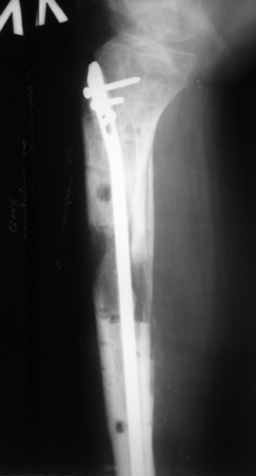

|  |  |  |  status localis на 14.11.08 (В ране визуализируется сухожилие.) | Больной А, 40 лет, находится в клинике с 15.10.08 с диагнозом: Сочетанная травма. Ушиб головного мозга лёгкой степени тяжести. Компрессионные переломы тел 12 грудного и 5 поясничного позвонков без неврологических осложнений. Закрытый внутрисуставной многооскольчатый перелом дистальных метаэпифизов обеих костей правой голени со смещением. Открытый внутрисуставной многооскольчатый перелом дистальных метаэпифизов обеих костей левой голени со смещением (см. Р-граммы). Хронический алкоголизм. Доставлен СМП после падения с 5-го этажа (не суицид). При поступлении состояние тяжелое. Глубокое оглушение. Дыхание самостоятельное, адекватное. Гемодинамика стабильная. По внутренней поверхности левой голени, в нижней трети, рвано-ушибленная рана 10-6 см, из раны выстоит проксимальный отломок большеберцовой кости, рана обильно загрязнена землёй. Интенсивная терапия в условиях реанимационного отделения, вытяжение за правую пяточную кость, параартериальная блокада обеих нижних конечностей, гипсовая лонгета на левую нижнюю конечность, ас-повязка на рану. Через 4 часа после поступления оперирован: после неоднократного промывания раны тёплой проточной водой с мылом, антисептиками, при ревизии определяется земля в канале проксимального отломка на глубину 3 см..., отсутствие надкостницы на концах дистального и проксимального отломков на 3 см. Удалено значительное количество мелких костных фрагментов, перемешанных с землёй, выполнена ПХО раны, резекция проксимального конца большеберцовой кости на 3,5 см, ЧКДО аппаратом Илизарова. Рана не ушивалась. В последующем перевязки раны с "Левомеколь", через 3 недели с момента травмы в ране определялись грануляции, нежизнеспособный конец дистального отломка. 10.11.08 ВХО раны, резекция дистального отломка на 3 см, перемонтаж аппарата наружной фиксации (см. Р-граммы). Отломки сближены на 2 см (остеотомию малоберцовой не делали). В настоящее время (5 сутки после операции) незначительное количество серозного отделяемого из раны, имеется дефект кости 4 см (см. Р-граммы). В последующем склоняемся к перемонтажу аппарата наружной фиксации, остеотомии малоберцовой кости в области повреждения, сближении отломков. По заживлению раны удлинение левой голени на 4 см. Однако, некоторыми высказывалось мнение о необходимости артродеза. Представляем рентгенограммы левой голени при поступлении, после повторного оперативного лечения и фото st.localis на 14.11.08. Будем очень благодарны за критику, комментарии, пожелания и мнения о дальнейшей тактике лечения.

В случае гладкого заживления раны, при условии положительного решения вопроса с металлом, планируем перемонтаж аппарата Илизарова, дополнительную резекцию дистального отломка, выведение полокости голеностопного сустава в правильное положение (см. боковую Р-грамму), одномоментно остеотомия большеберцовой кости. После восстановления длинны голени, по всей видимости, артродез голеностопного сустава.

Рентгенограммы прилагаются. Фото местного статуса выложу в ближайшее время.